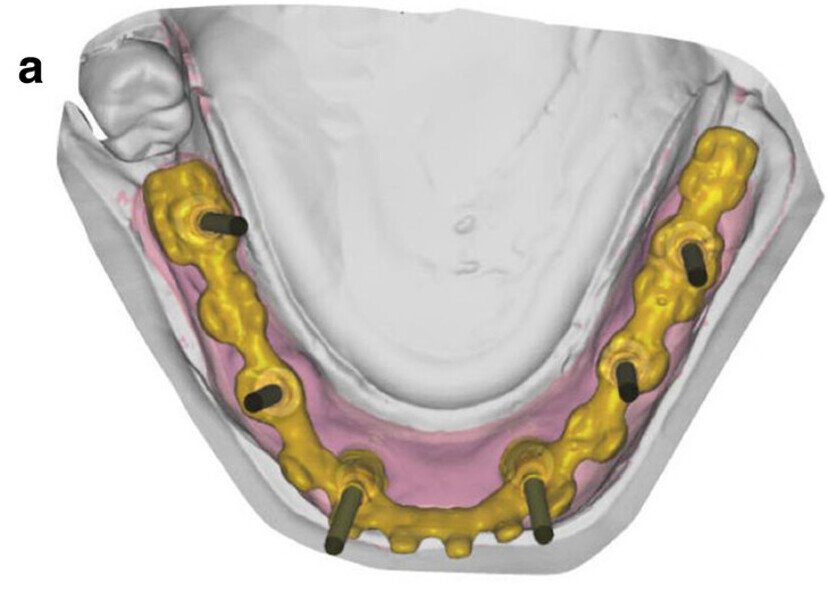

Fig. 5a: CAD/

CAM-fabricated surgical guides: tooth- and mucosa- supported (a) and implant- and mucosa-supported (b).